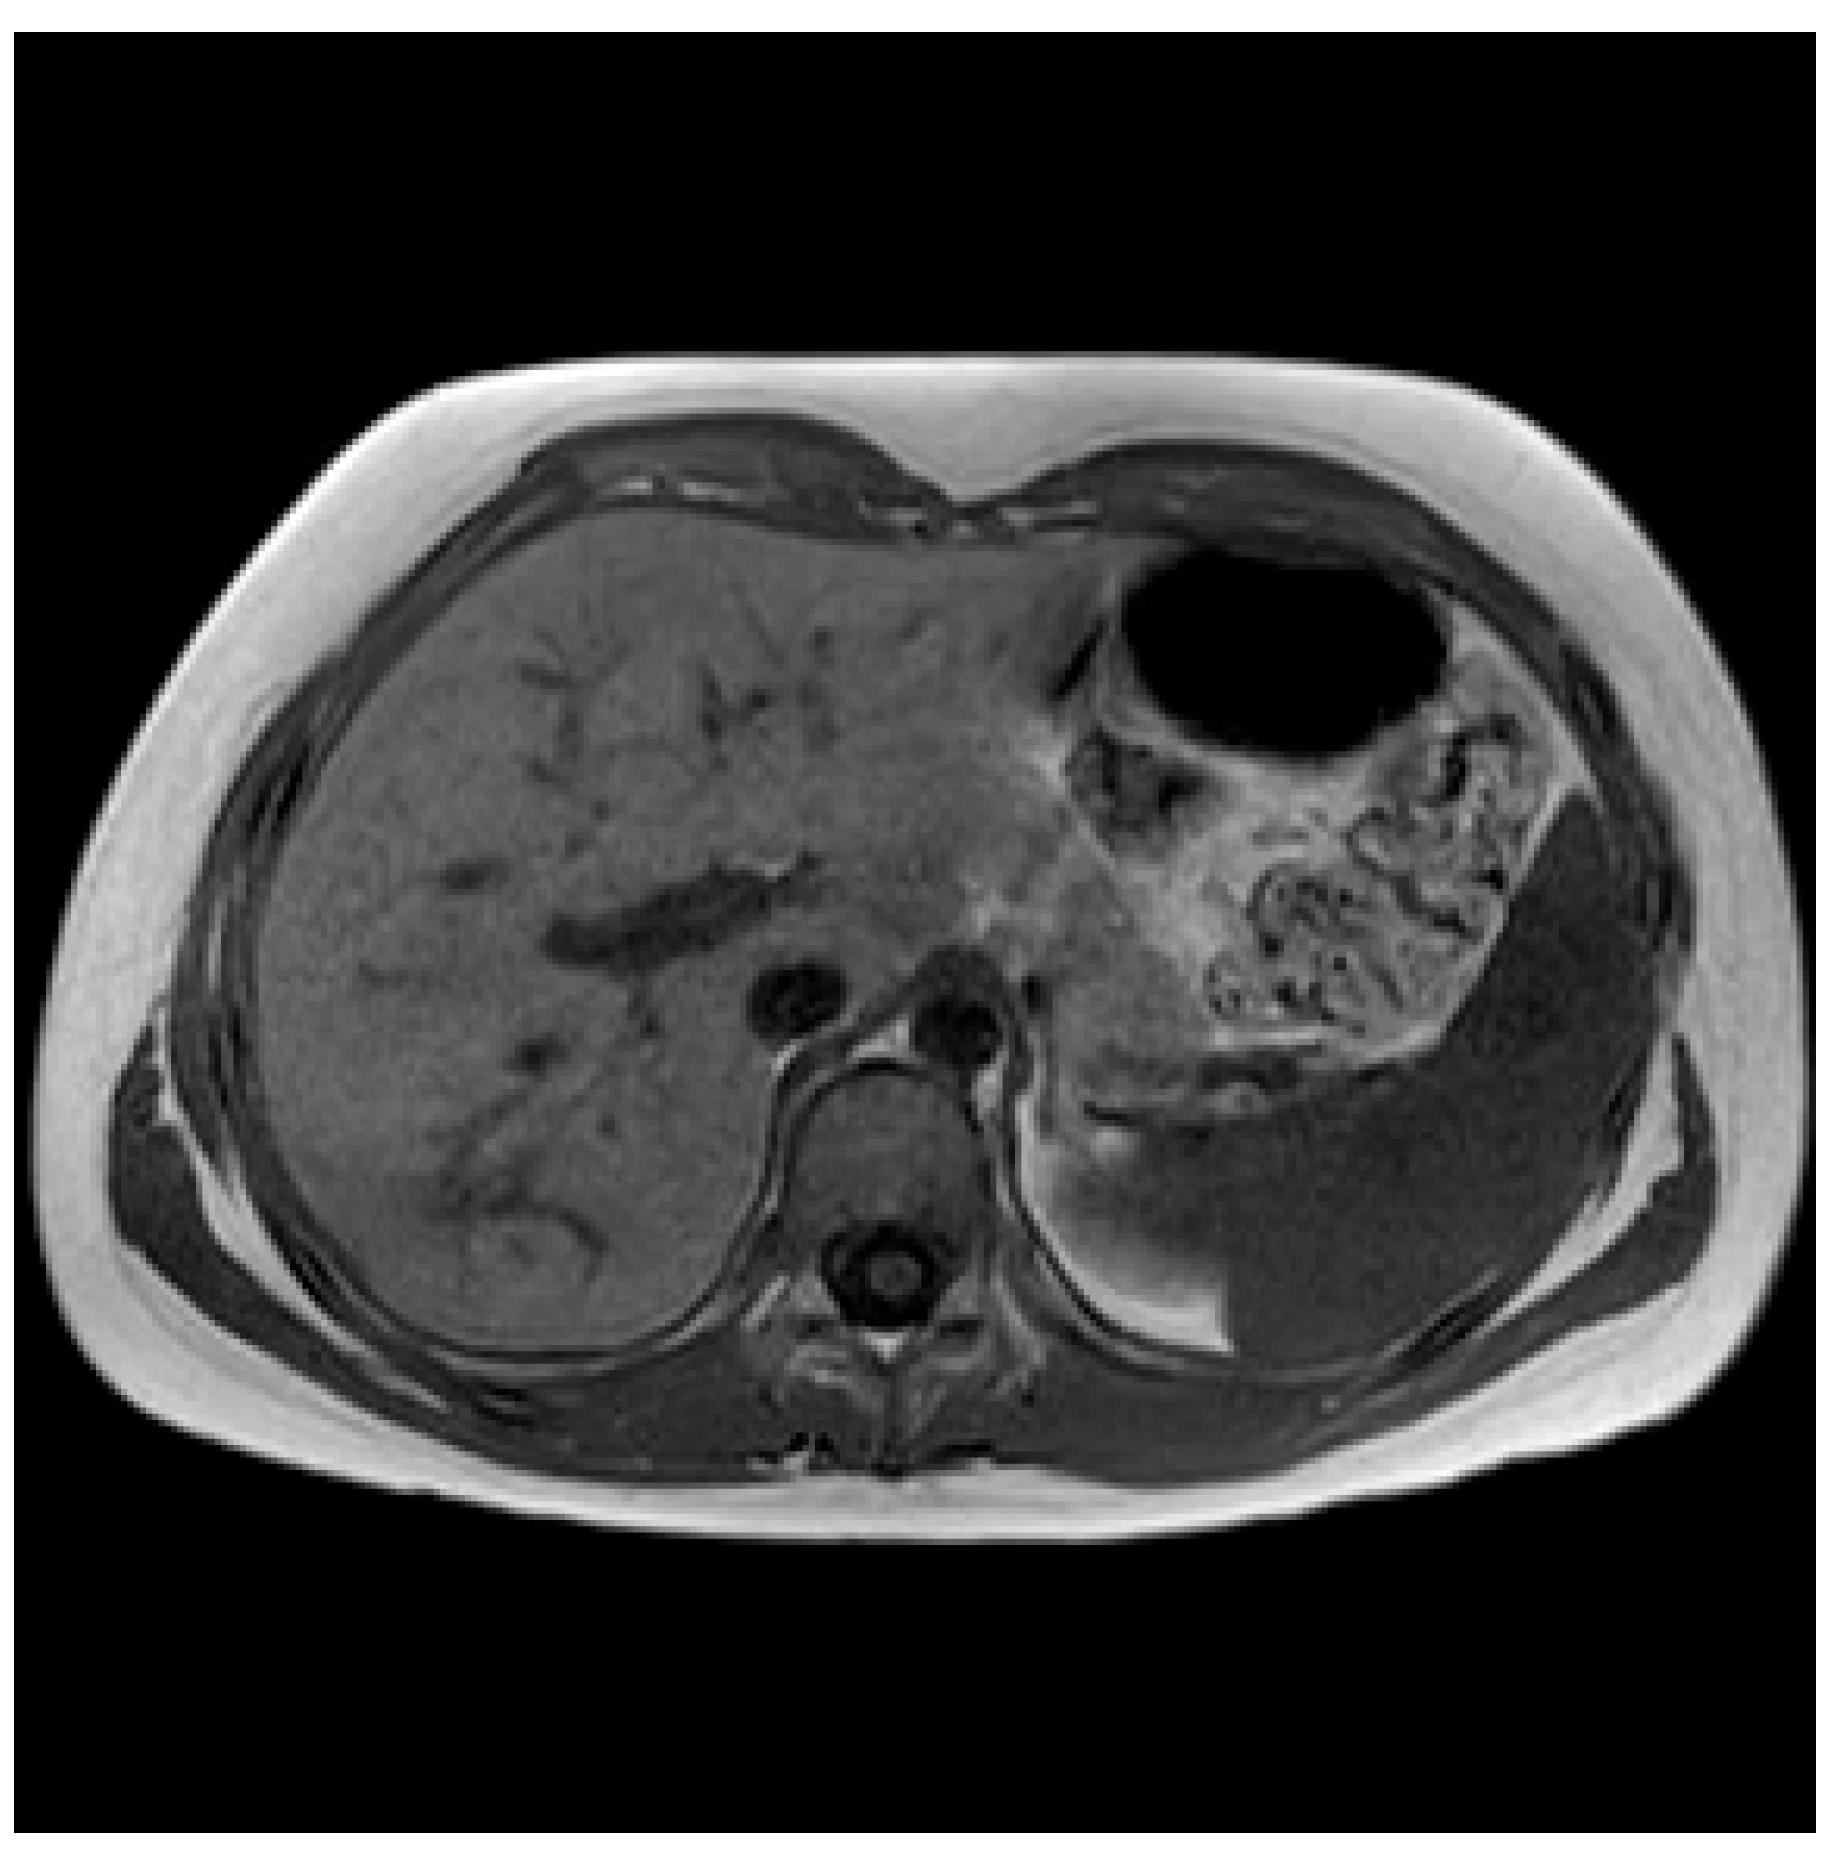

2.1.2. Initial Assessment and Hematological and Radiological Investigations

2.1.3. Microbiology Investigations